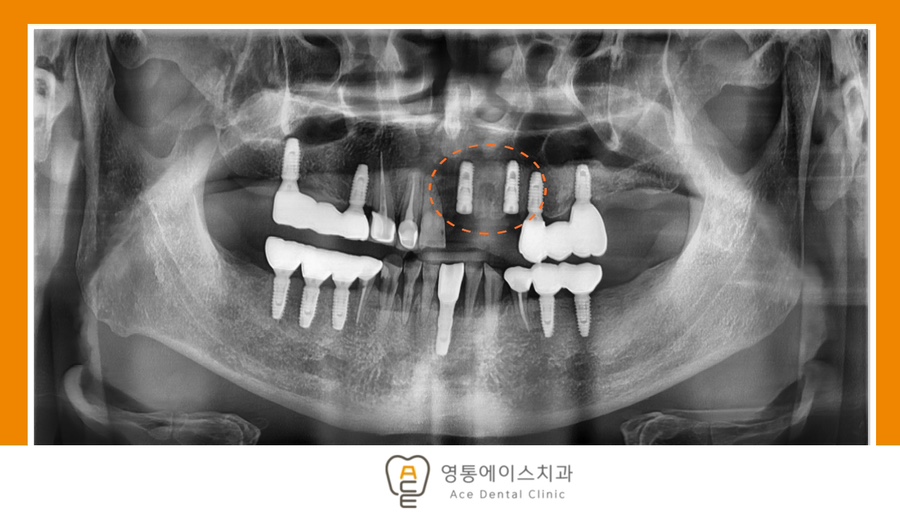

치료 전 사진 / 2025. 09. 09

치료 전, 후 사진 / 2025. 09. 09 ~ 2025.11.17

*치료 기간 : 2025. 09. 09 ~ 2025.11.17